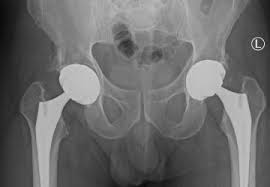

Precision hip replacement focuses on accurate planning, alignment, and implant positioning. Therefore, surgeons use detailed imaging and measurements to understand joint structure before surgery. Moreover, precise execution helps restore natural joint mechanics. As a result, patients experience smoother movement and improved stability. In addition, minimizing deviation during surgery reduces uneven implant wear. Consequently, precision hip replacement offers enhanced comfort and long-term performance for patients undergoing surgery in Bhopal.

The precision hip replacement process begins with detailed consultation and imaging studies. Therefore, surgeons analyze joint alignment, bone quality, and overall health. Moreover, personalized surgical planning ensures accurate implant selection and positioning. As a result, the procedure restores joint mechanics effectively. In addition, careful intraoperative monitoring enhances safety and accuracy. Consequently, precision hip replacement in Bhopal delivers controlled and reliable surgical execution.